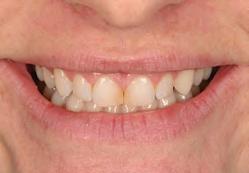

A 31-year-old woman presented with cosmetic concerns regarding her smile and requested a conservative enhancement. After clinical and radiographic analysis, digital 35mm photographs were taken and reviewed by the restorative clinician, technician, and surgeon (Fig 1). A digital impression was taken of the maxillary and mandibular arches using an intraoral scanner (Trios 3, 3Shape; Fig 2), and a smile design was developed with NemoSmile Design 3D software (Nemotec; Fig 3a). This allows for a facially driven smile frame to be created using reference lines of facial and smile proportions and natural teeth shapes and textures from the digital library (Fig 3b).

Fig 1 Preoperative clinical views of a 31-year-old woman presenting with diastemas and limited tooth visibility. (top) Portrait. (center row) Intraoral views. (bottom row) Smile.

4b). This matrix was used to create an intraoral motivational mock-up with bis-acryl composite (Luxatemp Ultra, DMG). This additive mock-up provides the interdisciplinary team with an intraoral translation for evaluation (Fig 5). Upon evaluation of the digital smile frame and the clinical translation, it was determined that multiple esthetic and restorative requirements were necessary for an optimal biologic framework, and the interdisciplinary team determined the best sequence for these procedures. The patient was presented with the interdisciplinary treatment possibilities that included restoring the maxillary anterior teeth and premolars with a minimally

invasive preparationless procedure or with less conservative veneer preparations. The restorative materials discussed included injectable resin composites and ceramic (ie, feldspathic, pressable, machinable). For an optimal biologic framework and health, it was determined that connective tissue grafting would be necessary for treatment of the recessiontype defects on the maxillary left central and lateral incisors, canine, and premolars. The patient opted for the conservative preparationless composite veneers using the injectable resin technique followed by a connective tissue surgical procedure using the tunneling technique.